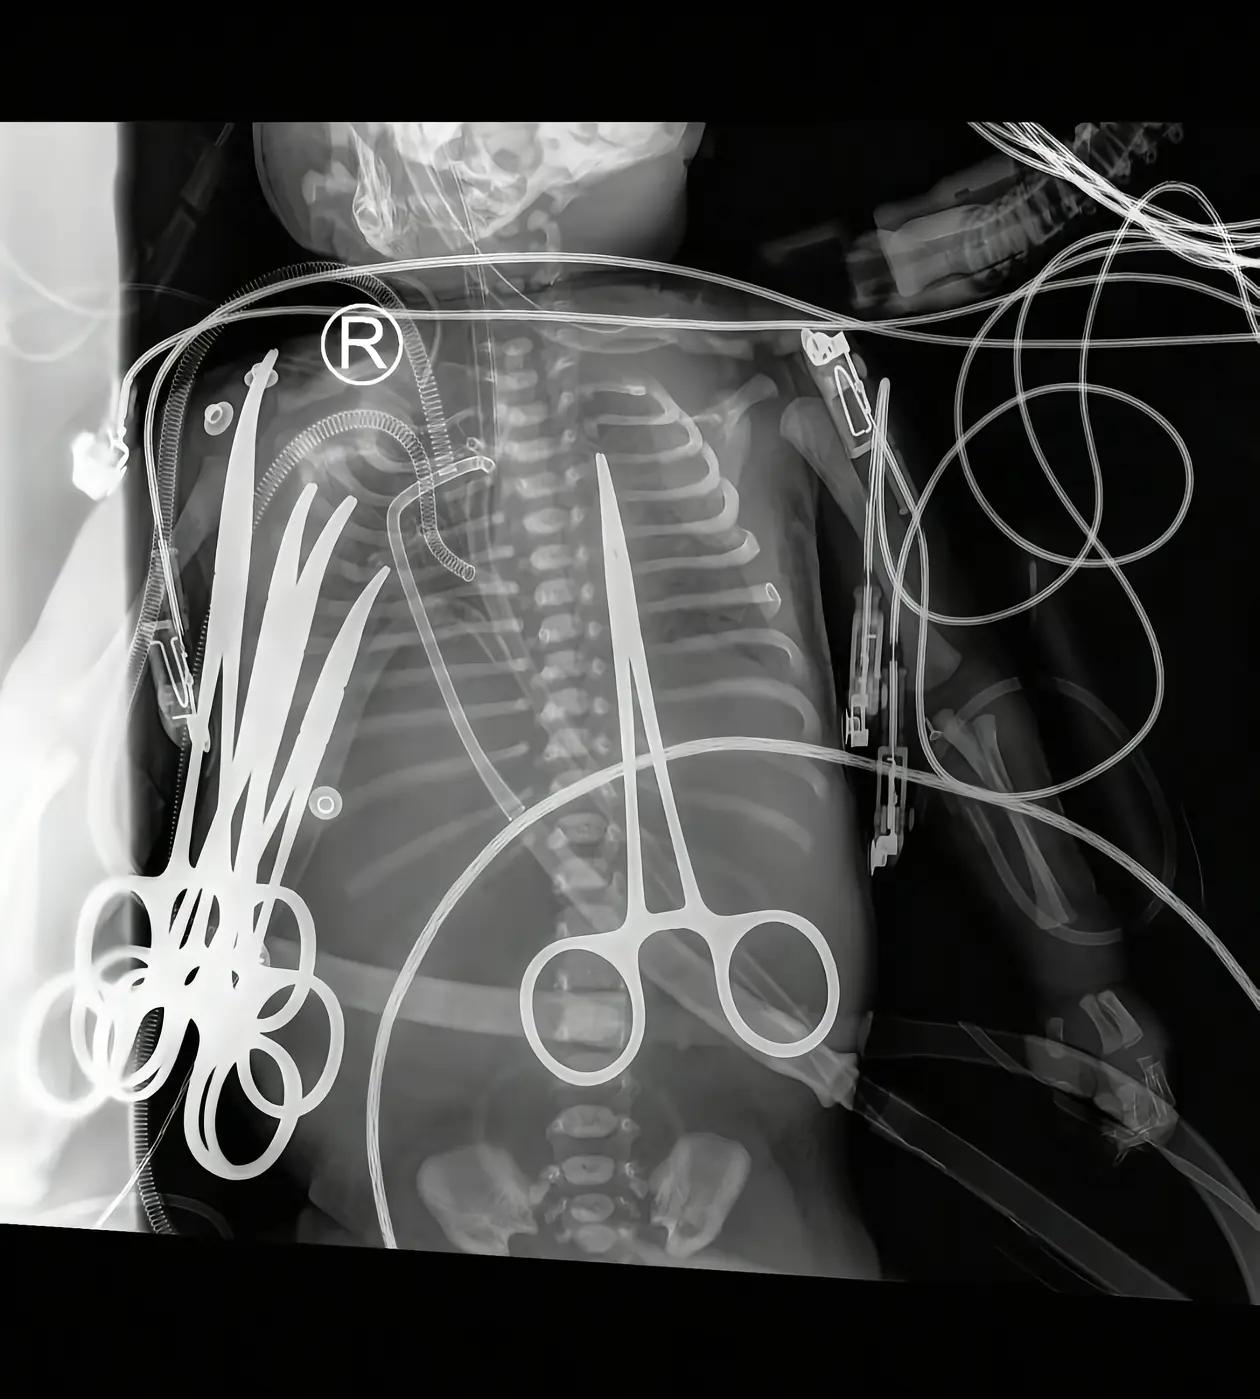

家属委托刘良团队尸检追真相 出生仅22天的生命,在两次开胸手术后戛然而止。11月28日,网友@小暖崽妈妈 发布视频实名举报中南大学湘雅二医院心脑血管外科主任吴某某,揭开了这起令人痛心的医疗纠纷,引发全网关注。 时间回溯至11月5日,女婴因心脏相关问题就诊,主刀医生吴某某告知家属“手术成功率90%以上”“孩子心脏正常,只需切除窄血管,是简单手术”,家属随即同意手术。然而这场被描述为“简单”的手术,却成了小生命的劫难。11月21日,医院在完成第二次手术后告知家属“手术成功”,但不久后便紧急通知患儿病危,让家属陷入焦灼。更让家属无法接受的是,11月24日,医生在未提前告知的情况下为孩子拔管,最终女婴不幸离世。 “两次手术都说成功,可我们翻看医嘱单才发现,孩子术后每天都处于病危状态,一直在抢救。”孩子父亲在接受采访时痛陈,女儿离世后,家属想第一时间探视遗体却遭阻拦,被要求前往太平间查看,这一遭遇让他们对诊疗过程产生诸多质疑。目前,家属的核心诉求明确:查明孩子离世的真正原因,讨回公道。 在当地卫健委的组织下,家属已与院方展开会谈,双方共同决定对女婴进行尸检,而承担此次尸检任务的,正是此前负责宁波离世女婴“小洛熙”尸检的华中科技大学同济医学院刘良教授团队。作为业内权威,刘良团队曾完成世界首例新冠肺炎逝者遗体解剖,30余年法医生涯中检案数千次,鉴定结果备受认可,其“让遗体说话,用证据还原真相”的专业精神,成为家属寻求公道的重要寄托。 据悉,宁波5月龄女婴小洛熙此前在心脏手术后离世,家属同样选择委托刘良团队进行尸检,目前相关尸检工作已完成。此次湖南22天女婴事件中,刘良团队的介入让公众对真相的揭开充满期待。 截至目前,湘雅二医院尚未针对此事发布官方回应,关于手术是否存在违规操作、病情告知是否充分、拔管行为是否合规等核心疑问,仍有待尸检结果给出科学答案。这场跨越两地的医疗纠纷,牵动着无数网友的心,大家纷纷呼吁“查明真相,还孩子和家属一个公道”,相关进展仍在持续关注中。